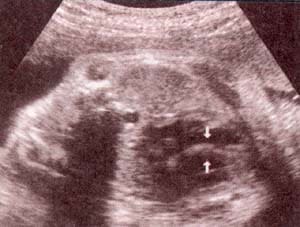

| fig 30. -(a). septum i-v. septum i-v. 32 semana | fig. 30.– (b). septum i-v íntegro entre las flechas. 35 semanas |